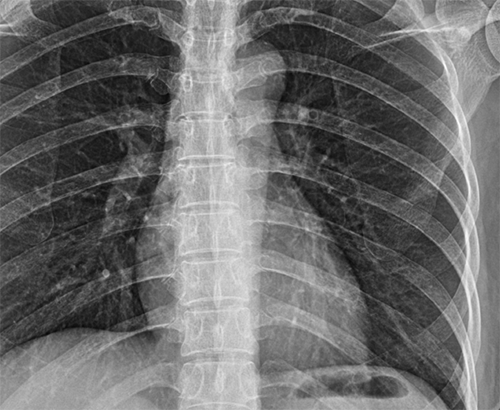

- 흉부 X-ray: 기본적으로 갈비뼈 골절 여부 확인 시 가장 많이 활용됩니다.

- CT(컴퓨터 단층 촬영): X-ray에서 확인이 어려운 미세골절, 연골 손상, 내부 출혈까지 파악 가능.